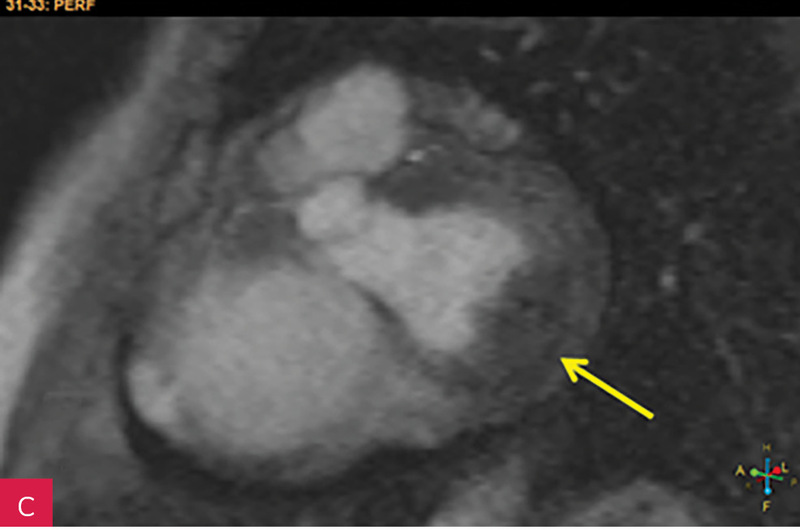

Rycina 8A, B. Obrazy rezonansu magnetycznego w projekcji pięciojamowej (A) i dwujamowej (B) z późnym wzmocnieniem kontrastowym – widoczna zmiana ulegająca brzeżnemu wzmocnieniu kontrastowemu. Całość obrazu wskazuje na serowate zwapnienie pierścienia mitralnego (CCMA)

W celu weryfikacji zmiany i oceny charakterystyki tkanki wykonano CMR,

w którym stwierdzono w dolno-bocznej części pierścienia mitralnego od strony światła lewej komory zmianę odpowiadającą morfologicznie CCMA, obejmującą 7,3 cm obwodu pierścienia mitralnego, o grubości w osi krótkiej do 25 mm, w osi długiej do 21 mm; zmiana ulegała brzeżnemu wzmocnieniu kontrastowemu i powodowała ograniczenie ruchomości tylnego płatka zastawki mitralnej, obejmowała struny ścięgniste mięśnia brodawkowatego tylno-przyśrodkowego. Ponadto uwidoczniono znacznie powiększone przedsionki z istotnym włóknieniem – jak w restrykcji (ryc. 7, 8).